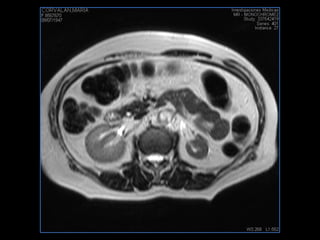

PROTOCOLO pancreas/ riñon AXIAL fat sat /AX in phase out phase AX T1 +SAG T2  COR T2, CON   GADOLINIO :  COR T1+AX T1(DIN) SAT: NO  FASE: RL THK: 4MM  COIL:  GAP: (FACTOR 1.4) 1MM FOV: 40 CM NEX:2 SINCRONIZACION RESPIRATORIA EN 3 O 4 CICLOS ALE